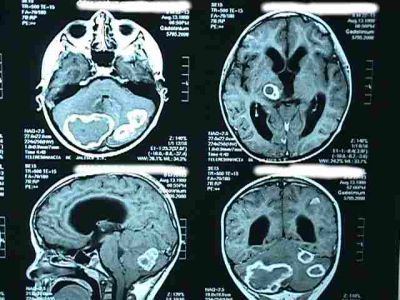

Por otro lado, los avances de medicina en el Perú han sido de una envergadura importante tenemos entre los progresos tecnológicos las prótesis, las ayudas de diagnóstico por imágenes, las ayudas biomecánicas que han contribuido a desarrollar nuevas técnicas operatorias. Asimismo se han mejorado las aplicaciones de las anestesias, asepsia y antisepsia.[4]